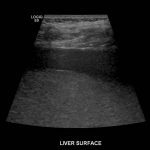

- Hepatomegaly with coarsened hepatic parenchymal echotexture

Hepatomegaly with coarsened hepatic parenchymal echotexture, concerning for cirrhosis.